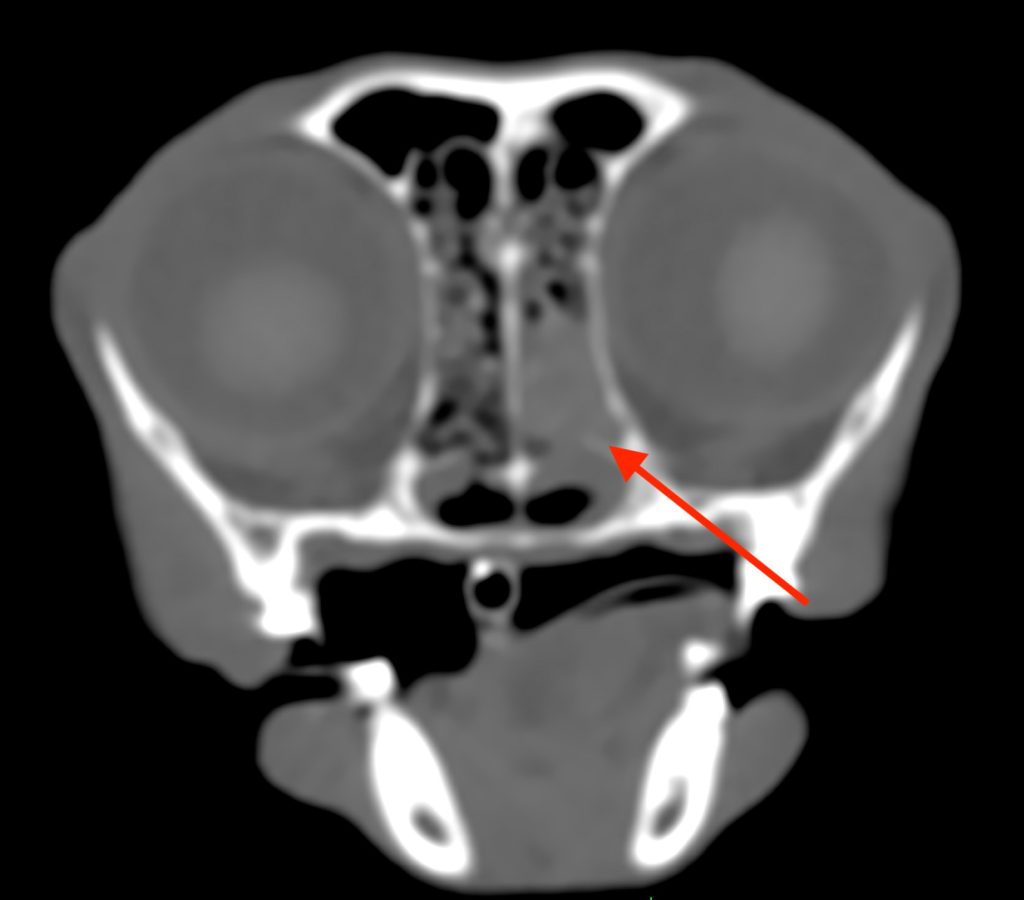

単純CT検査では、鼻腔内に貯留物が認められました。

造影CT検査では、鼻粘膜の造影増強は認められましたが、貯留物は造影増強が認められず、

炎症による鼻汁の貯留が疑われました。また、異物や腫瘍を疑う所見は認められず、

鼻腔の周りの副鼻腔という空間にも、炎症などの異常は認められませんでした。

以上の所見から、慢性鼻炎と診断しました。